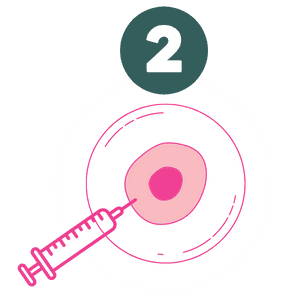

O processo de análise começa com a observação detalhada das imagens geradas pelo ultrassom morfológico. Isso inclui verificar a normalidade do útero, a integridade da placenta, membranas uterinas, o desenvolvimento fetal, a adequada frequência cardíaca fetal e o fluxo sanguíneo útero-placentário-fetal. O ultrassonografista avalia a anatomia do bebê, certificando-se de que os ossos, órgãos e outros sistemas, como o coração, cérebro, estômago e rins estejam se desenvolvendo conforme esperado. É igualmente importante observar a presença de batimentos cardíacos regulares e os movimentos respiratórios fetais no terceiro trimestre da gestação.

- Ossos e órgãos: Verificação de desenvolvimento proporção e crescimento.